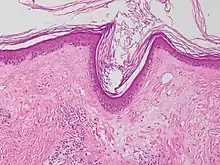

Micrograph of a vacuolar interface dermatitis with dermal mucin, as may be seen in lupus. H&E stain.

Vacuolar interface dermatitis (VAC, also known as liquefaction degeneration, vacuolar alteration or hydropic degeneration) is a dermatitis with vacuolization at the dermoepidermal junction, with lymphocytic inflammation at the epidermis and dermis.[1]

Generally/Not otherwise specified Typical findings, called "vacuolar interface dermatitis":[2]

• Mild inflammatory cell infiltrate along the dermoepidermal junction (black arrow in image)

• Vacuolization within the basal keratinocytes (white arrow in image)

• Often necrotic, predominantly basal, individual keratinocytes, manifesting as colloid or Civatte bodies